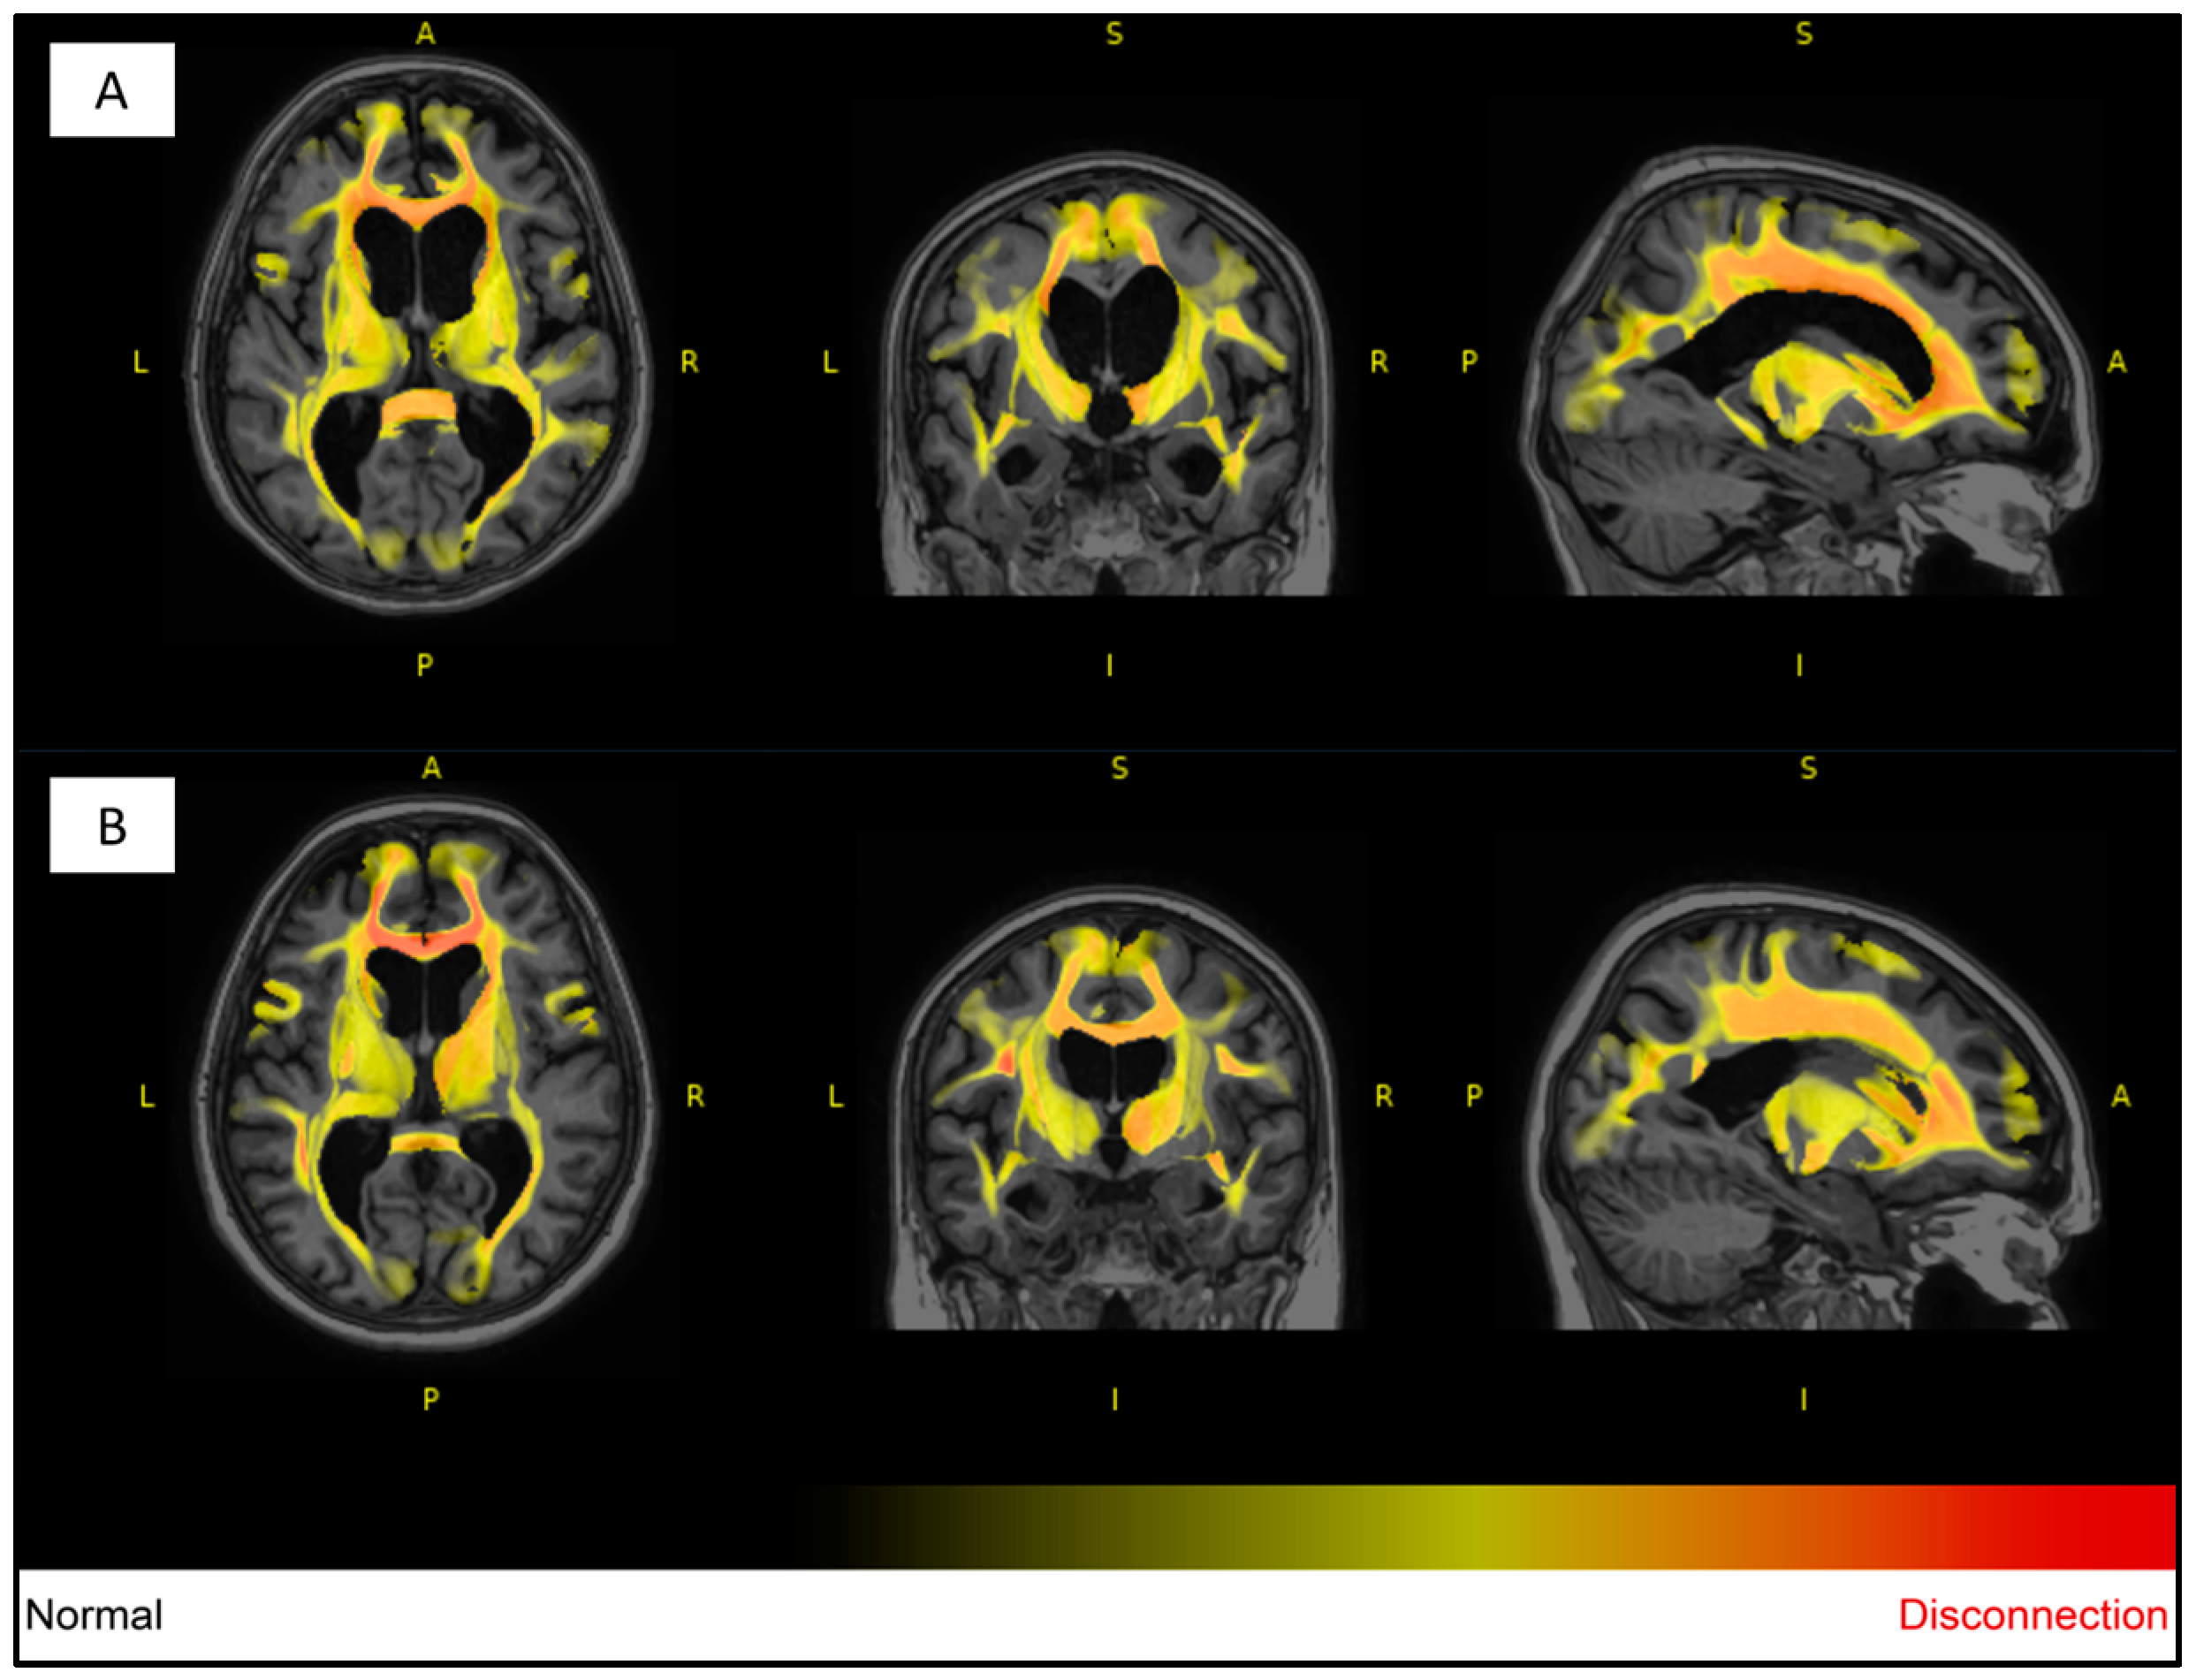

For white matter hyperintensity analysis, we used the volBrain’s DeepLesionBrain (DLB) pipeline (https://www.volbrain.upv.es (accessed on 8 February 2023)). VolBrain is an MRI brain volumetry software that operates automatically and can offer brain structure volumes without human involvement; it was developed by José V. Manjón (IBIME, UPV, Valencia, Spain) and Pierrick Coupé (LaBRI UMR 5800, Université de Bordeaux, CNRS, Bordeaux, France). VolBrain employs an entirely automated pipeline for volumetric brain analysis based on multi-atlas label fusion technology, which can provide accurate volumetric information at various levels of detail in a short time [25]. WMH segmentation starts with image denoising, which is followed by inhomogeneity correction, spatial registration, intensity normalization, and intracranial cavity extraction by employing the Montreal Neurological Institute algorithm (MNI). The tissue is then segmented using a multi-template fusion atlas strategy, originating from a library that was produced by manually segmenting 43 patients by an expert radiologist using multimodal MRI data. Voxels surpassing a specific threshold are lesion candidates; the volBrain program automatically handles thresholding and voxel processing. The identified lesions are allocated into four anatomical regions: paraventricular, deep white, juxtacortical, and infratentorial, which are further divided into cerebellar and medullar regions. The number, volume, and distribution of each lesion are recorded. The process concludes with the generation of an automated report containing the lesion load, number of lesions per class, and screenshots of the processed images. Additionally, DLB provides the probability of disconnection caused by the detected lesions for 64 white matter tracts and estimates a disconnectome map based on the HCP1065 atlas [26]. Figure 1, Figure 2 and Figure 3 demonstrate MRI FLAIR sequence segmentation using volBrain DLB.

Figure 3.

Segmented T1W MRI imaging of the 77-year-old female monozygotic twin pair in 2022 using DLB; most of the analyzed tracts of the affected twin (A) have been affected by lesions (first row), and more than a third of the analyzed tracts were completely unaffected by lesions in the unaffected pair (B) (second row). The degree of WMH impact on each tract is visualized through a heat map, with yellow and red indicating increasing severity. Image from the Semmelweis University Medical Imaging Centre. A: anterior; P: posterior; L: left; R: right.

Based on the DLB analysis using the HCP1065 atlas, out of the 64 analyzed white matter tracts in the affected twin pair, 60 tracts were affected by lesions (disconnection probability of above 55%), excluding left and right fornices and the cingulum parahippocampal tracts. On the other hand, in the unaffected twin pair, more than 33% of the analyzed tracts were unaffected by lesions (disconnection probability of 0%).

Many studies have reported various structural neuroimaging findings in T1- weighted, T2-weighted, and FLAIR images, including midbrain atrophy, atrophy of the superior cerebellar peduncle, and frontal and parietal cortical atrophy, which were present in the affected twin. Moreover, dilatation of the third and fourth ventricles and the aqueduct of Sylvius was also observed, which was present in the twin pair, with dominance in the affected twin. In addition, atrophy of the subthalamic nucleus is the most typical trait of PSP. The most characteristic pathological finding is the atrophy of the midbrain, which is demonstrated by the hummingbird sign as a result of rostral midbrain atrophy observed on mid-sagittal images, which was observed in the affected twin [6,36]. Interestingly, MRI signs of possible beginner PSP were suspected in the MRI imaging for the unaffected twin despite them being clinically asymptomatic, including narrow edematous signal disorder in the cerebellar tonsils and possible signs of NPH. The WMH analysis demonstrated remarkable differences between the twins, especially in the total, periventricular, and juxtacortical WMH lesion volume, which were higher in the PSP-affected twin. In addition, a remarkable decrease in brain volumes, mainly in total gray matter and frontal lobe volume except for temporal lobe volume, was observed. In the affected twin, a left cerebellar lacunar stroke was also observed, which referred to a vascular (possibly atherosclerotic) origin.